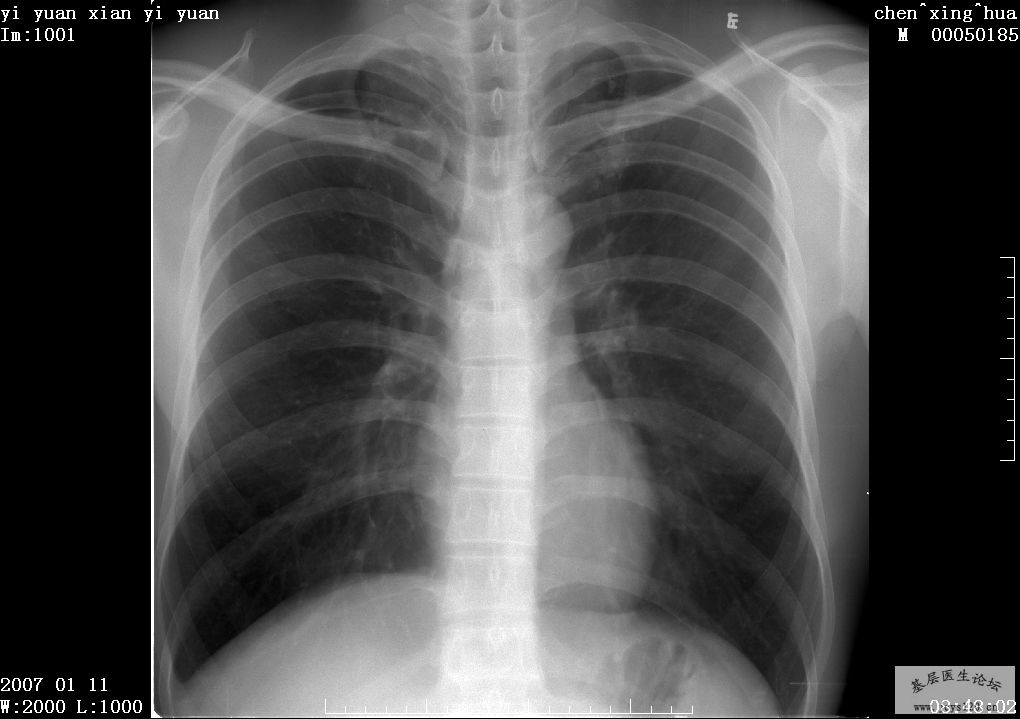

男,23岁 现病史:咳嗽1周?对烟尘越来越敏感。 既往史:电焊工4年,防护效果不理想,吸入大量烟尘;曾吸烟,因对烟尘敏感,感觉难受而戒烟。 影像表现: 双肺多发斑片影,边界较清,呈铺路石征表现,分布广 ... 阅读全文>